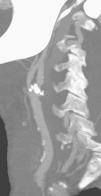

Fig. 3. --(A) Imagen de reconstrucción volumen rendering. (B) Reconstrucción mini-MIP de la arteria carótida izquierda. Estudio de angio-CT donde se observa la bifurcación carotídea y la porción proximal de ACI sin ninguna estenosis de significación.